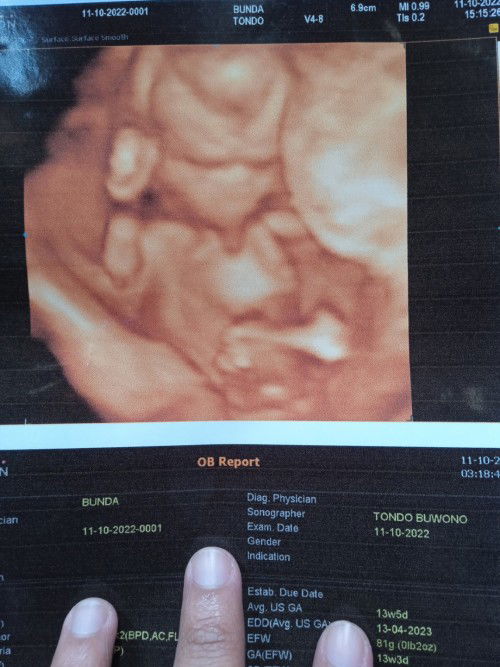

Halo bunda.. post foto buat kenangan aja. Alhamdulillah USG kandungan usia 13w5d udah kelihatan jelas bgt bun, bahkan jenis kelamin pun udah kelihatan.. seneng banget bun sekarang usia kandungan aku udah masuk 15w3d nih. do'ain sehat2 ya bunda.. semoga bunda2 semua juga diberikan kesehatan juga janin nya. amin.....#bantusharing